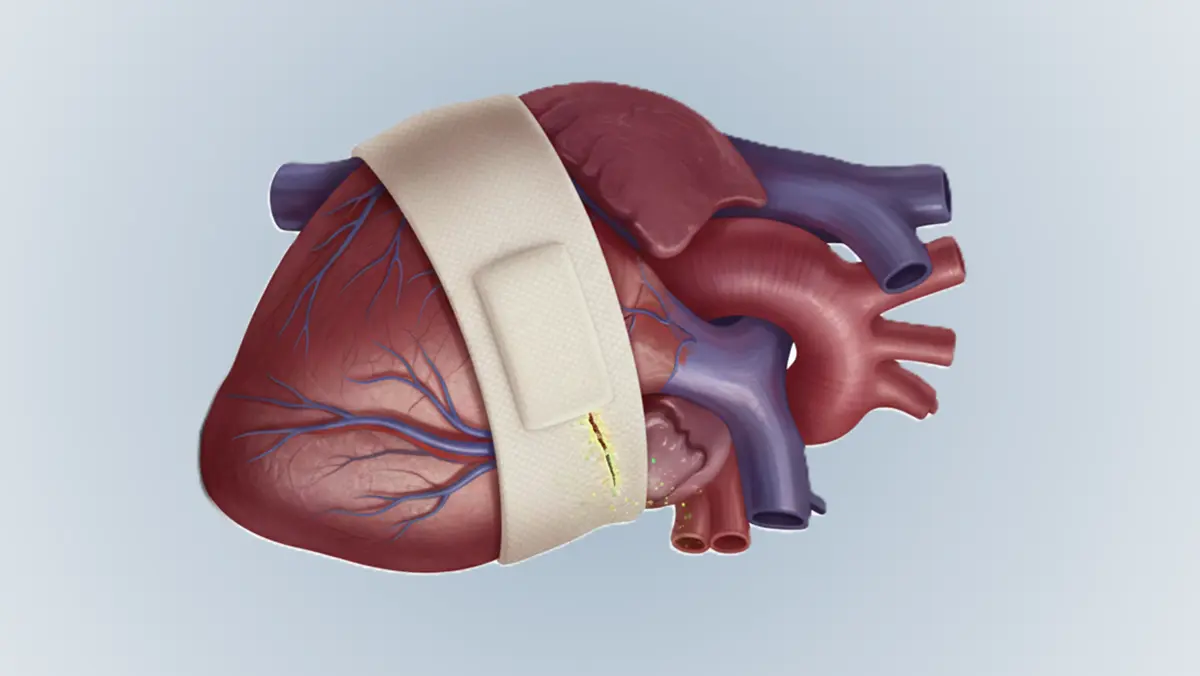

⚙️ در مواردی که تنگی رگ شدید باشد، ممکن است نیاز به آنژیوپلاستی و استنتگذاری باشد. در این روش، رگ تنگشده باز میشود و یک استنت (فنر فلزی) در آن قرار میگیرد تا جریان خون بهبود یابد. این روش کمتهاجمی و بسیار مؤثر است.

🏥 در تنگیهای بسیار شدید یا چندگانه، ممکن است جراحی بایپس لازم باشد. در این جراحی، مسیر جدیدی برای عبور خون ایجاد میشود تا ناحیه تنگشده دور زده شود. این روش برای بیماران با بیماری گسترده مناسب است.